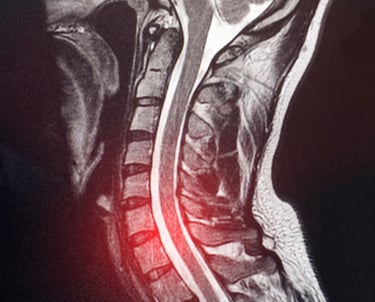

MRI shows unclear or suspicious lesions

MRI shows abnormal lesion

MRI or CT scan reports